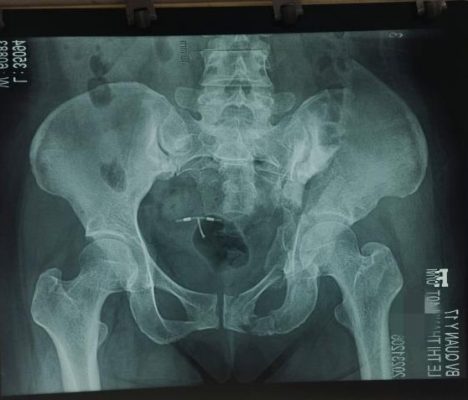

- Bệnh nhân được thăm khám, hội chẩn chuyên môn toàn Bệnh viện và liên Bệnh viện, dưới sự chủ trì của Giám đốc Bệnh viện, Phó giám đốc phụ trách khối ngoại, Bác sỹ chuyên khoa 2 Nguyễn Cao Viễn, Phó chủ nhiệm khoa Chấn thương Chỉnh hình Bệnh viện 115 – thành phố Hồ Chí Minh, xác định chẩn đoán là gãy cũ phức tạp ổ cối – khung chậu: gãy toác toàn bộ khung chậu, gãy bung toàn bộ trụ trước, gãy bung diện vuông, gãy di lệch lớn khuyết thần kinh toạ và diện nhĩ và sẽ đôi trần ổ cối, tổn thương mất vững nặng cả cột trụ trước sau.

Hình 1. Tổn thương khung chậu ổ cối trên phim cắt lớp vi tính và X-quang.